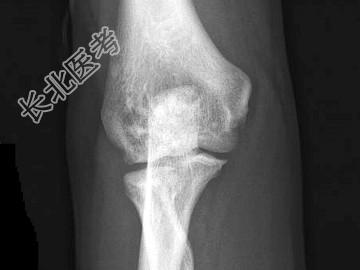

- 单项选择题男,34岁, 体检摄片如图所示,最可能的诊断是 ( )

A、氟骨症

B、转移性骨肿瘤

C、骨样骨瘤

D、骨岛

E、骨斑点症